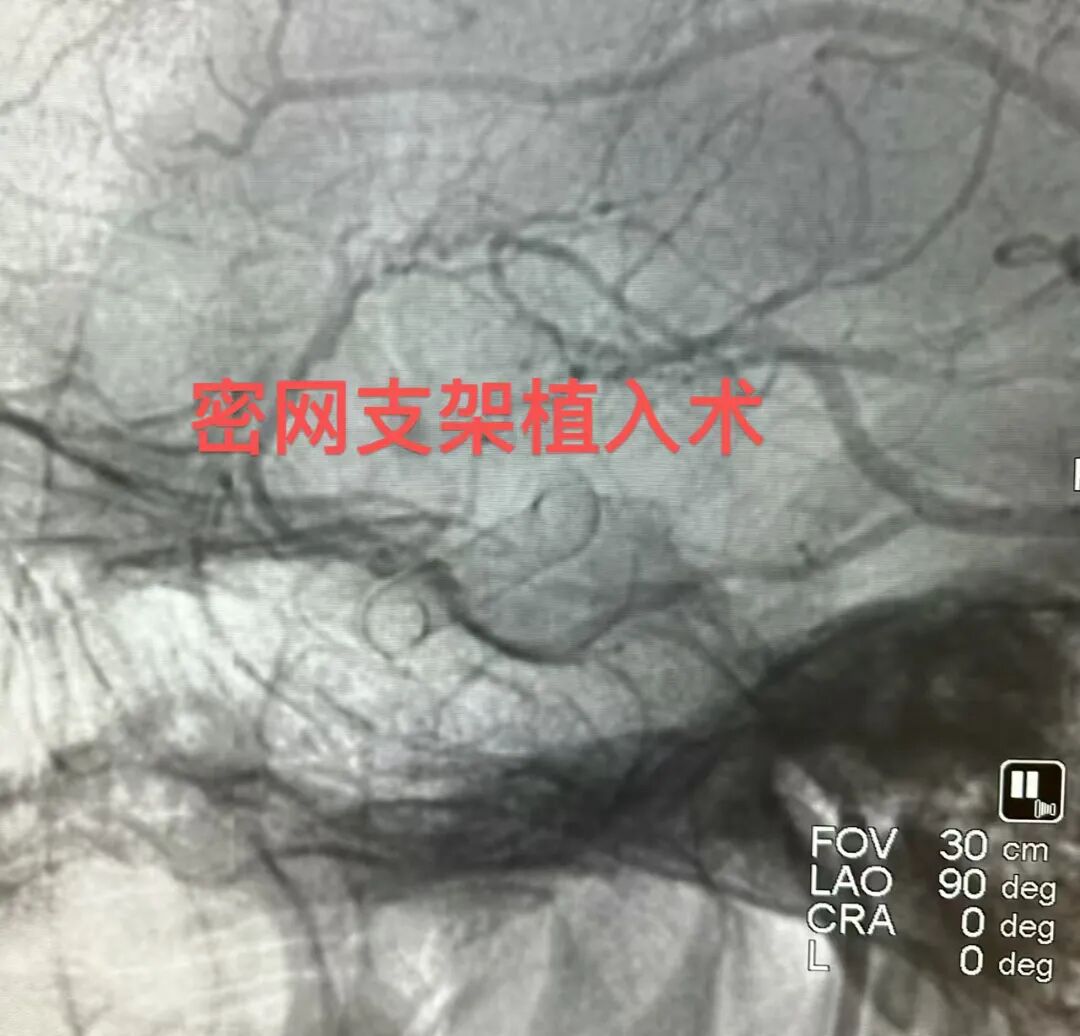

这位患者被确诊为脑动脉瘤,这颗颅内的“不定时炸弹”随时可能破裂,致死致残率极高。DSA明确显示:左侧颈内动脉眼段及后交通段各存在一枚动脉瘤。鉴于双动脉瘤位置邻近且位于同侧血管,为一次性处理并重建载瘤动脉,同时降低多枚支架植入或常规弹簧圈栓塞的复杂性与远期复发风险,经术前充分评估,选择行血流导向装置(密网支架)植入术。

手术室内,DSA机臂缓缓转动,屏幕上的血管影像清晰如画。导管精准到位,密网支架徐徐打开,如一张精密的“防护网”覆盖在瘤颈之上。无需填塞,仅靠改变血流动力学,便让动脉瘤内的血液“安静”下来,逐渐走向血栓闭合。

术后造影显示:支架打开贴壁良好,动脉瘤内造影剂明显滞留,载瘤动脉血流通畅。意味着神经内科介入团队成功将这颗“炸弹”拆除了。